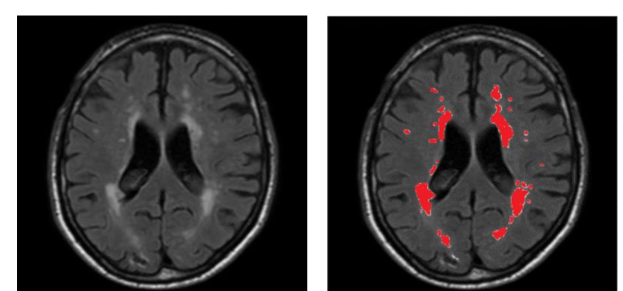

White matter lesions characterized by bilateral, mostly symmetrical hyperintensities, are commonly seen on FLAIR MRI of clinically healthy elderly people; furthermore, they have been repeatedly associated with various neurological and geriatric disorders such as mood problems and cognitive decline (Kim et al., 2008; Debette and Markus, 2010). Manual delineation of WMH area, as shown in Figure 1, is a reliable way to assess white matter abnormalities but this process is laborious and time-consuming for neuroradiologists and shows high intra-rater and inter-rater variability (Grimaud et al., 1996).

The WMH Segmentation Challenge 2017 111http://wmh.isi.uu.nl/ was held to compare state-of-the-art algorithms in conjunction with the 20th International Conference on Medical Image Computing and Computer Assisted Intervention (MICCAI 2017). This paper describes our winning entry to this challenge in detail, which was evaluated by the organizers on clinical datasets. The algorithm was containerized and applied to the test datasets by the challenge organizers, while the test sets remained unseen to us and other contestants. The test set includes 110 secret cases from five different MR scanners world-widely from three hospitals in the Netherlands and Singapore. Our approach to detecting WMH in MR images is based on an ensemble of convolution-deconvolution architecture (Long et al., 2015) with long-range connections (Ronneberger et al., 2015) which simultaneously classifies each pixel and locates objects of an input image. In our system, we implement a network architecture with 19 layers that are optimized for classifying and localizing the WMH. Ensemble models trained with random parameter initializations and shuffled data are employed for voting the pixel labels in the final evaluation.